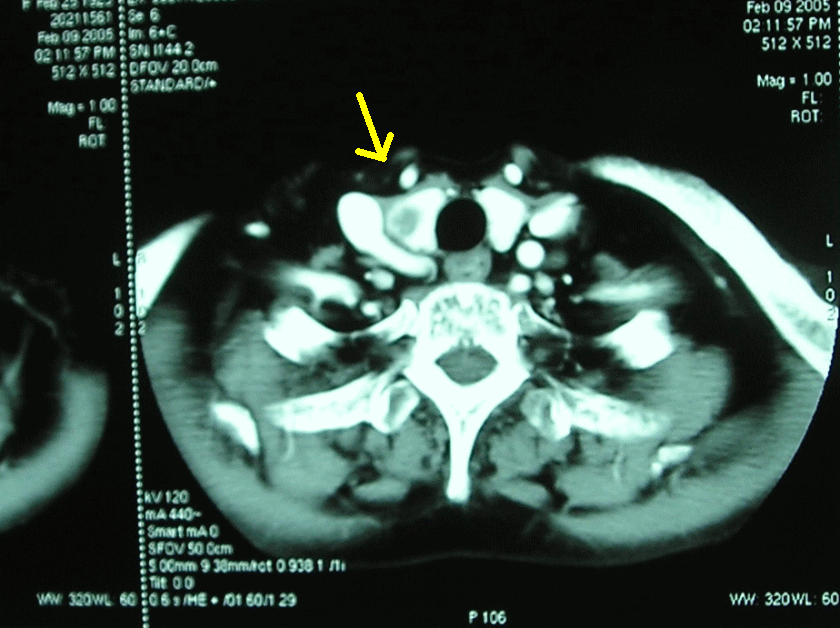

甲状腺 右葉の癌。

高齢で かつ悪性度も

低く このまま経過

観察となった。